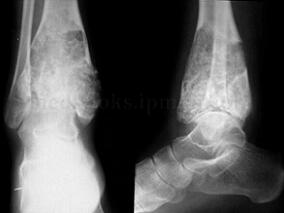

1小时条评论23岁女性患者,主因右胫骨下端肿瘤切除后3年复发,门诊收入院。同髋、膝、肩等部位骨肿瘤高发部位相比,胫骨下端的侵袭性和恶性肿瘤相对少见,原因何在?骨肿瘤切除后遗留大段骨缺损的重建问题,如何选择替代物? (1)病例介绍 :患者,女,23岁,主因右胫骨下端...